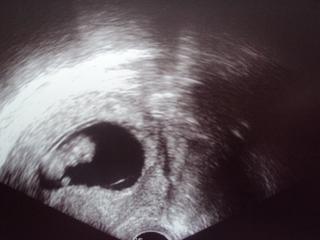

@lorreine - minulý týden byl gestační váček asi 7,4mm a už byl růst oproti minulé kontrole menší než "normální". Takže myslím, že ani moc nevyrostl za ten týden...Prosím na co je utrogestan a ascorutin? Je to na zastavení potratu nebo špíše na "hladší" průběh? Děkuji moc za zkušenost. Ještě se zeptám, jak dlouho jsi pak krvácela?

Ahojky holky, já už tu takovou dobu nebyla, že kdybych měla číst vše od té doby, tak bych tu byla dva dny, tak se nezlobte, že nebudu reagovat, akorát jsem zaregistrovala jahudky holčičku. Mě je totiž strašně zle, já jen ležím nebo zvracím a když už konečně na něco mám chuť tak si dvakrát zobnu a je mi zase zle, nemůžu nic dělat, strašně zanedbávám malou, nemůžu se jí věnovat, jak bych chtěla, ale nestrádá. Proto sem moc nechodím, jen hodím nějaké fotky a tím to skončí. Konečně mám fotku z UZ a krásně rosteme, jsem moc ráda, že je vše jak má 🙂